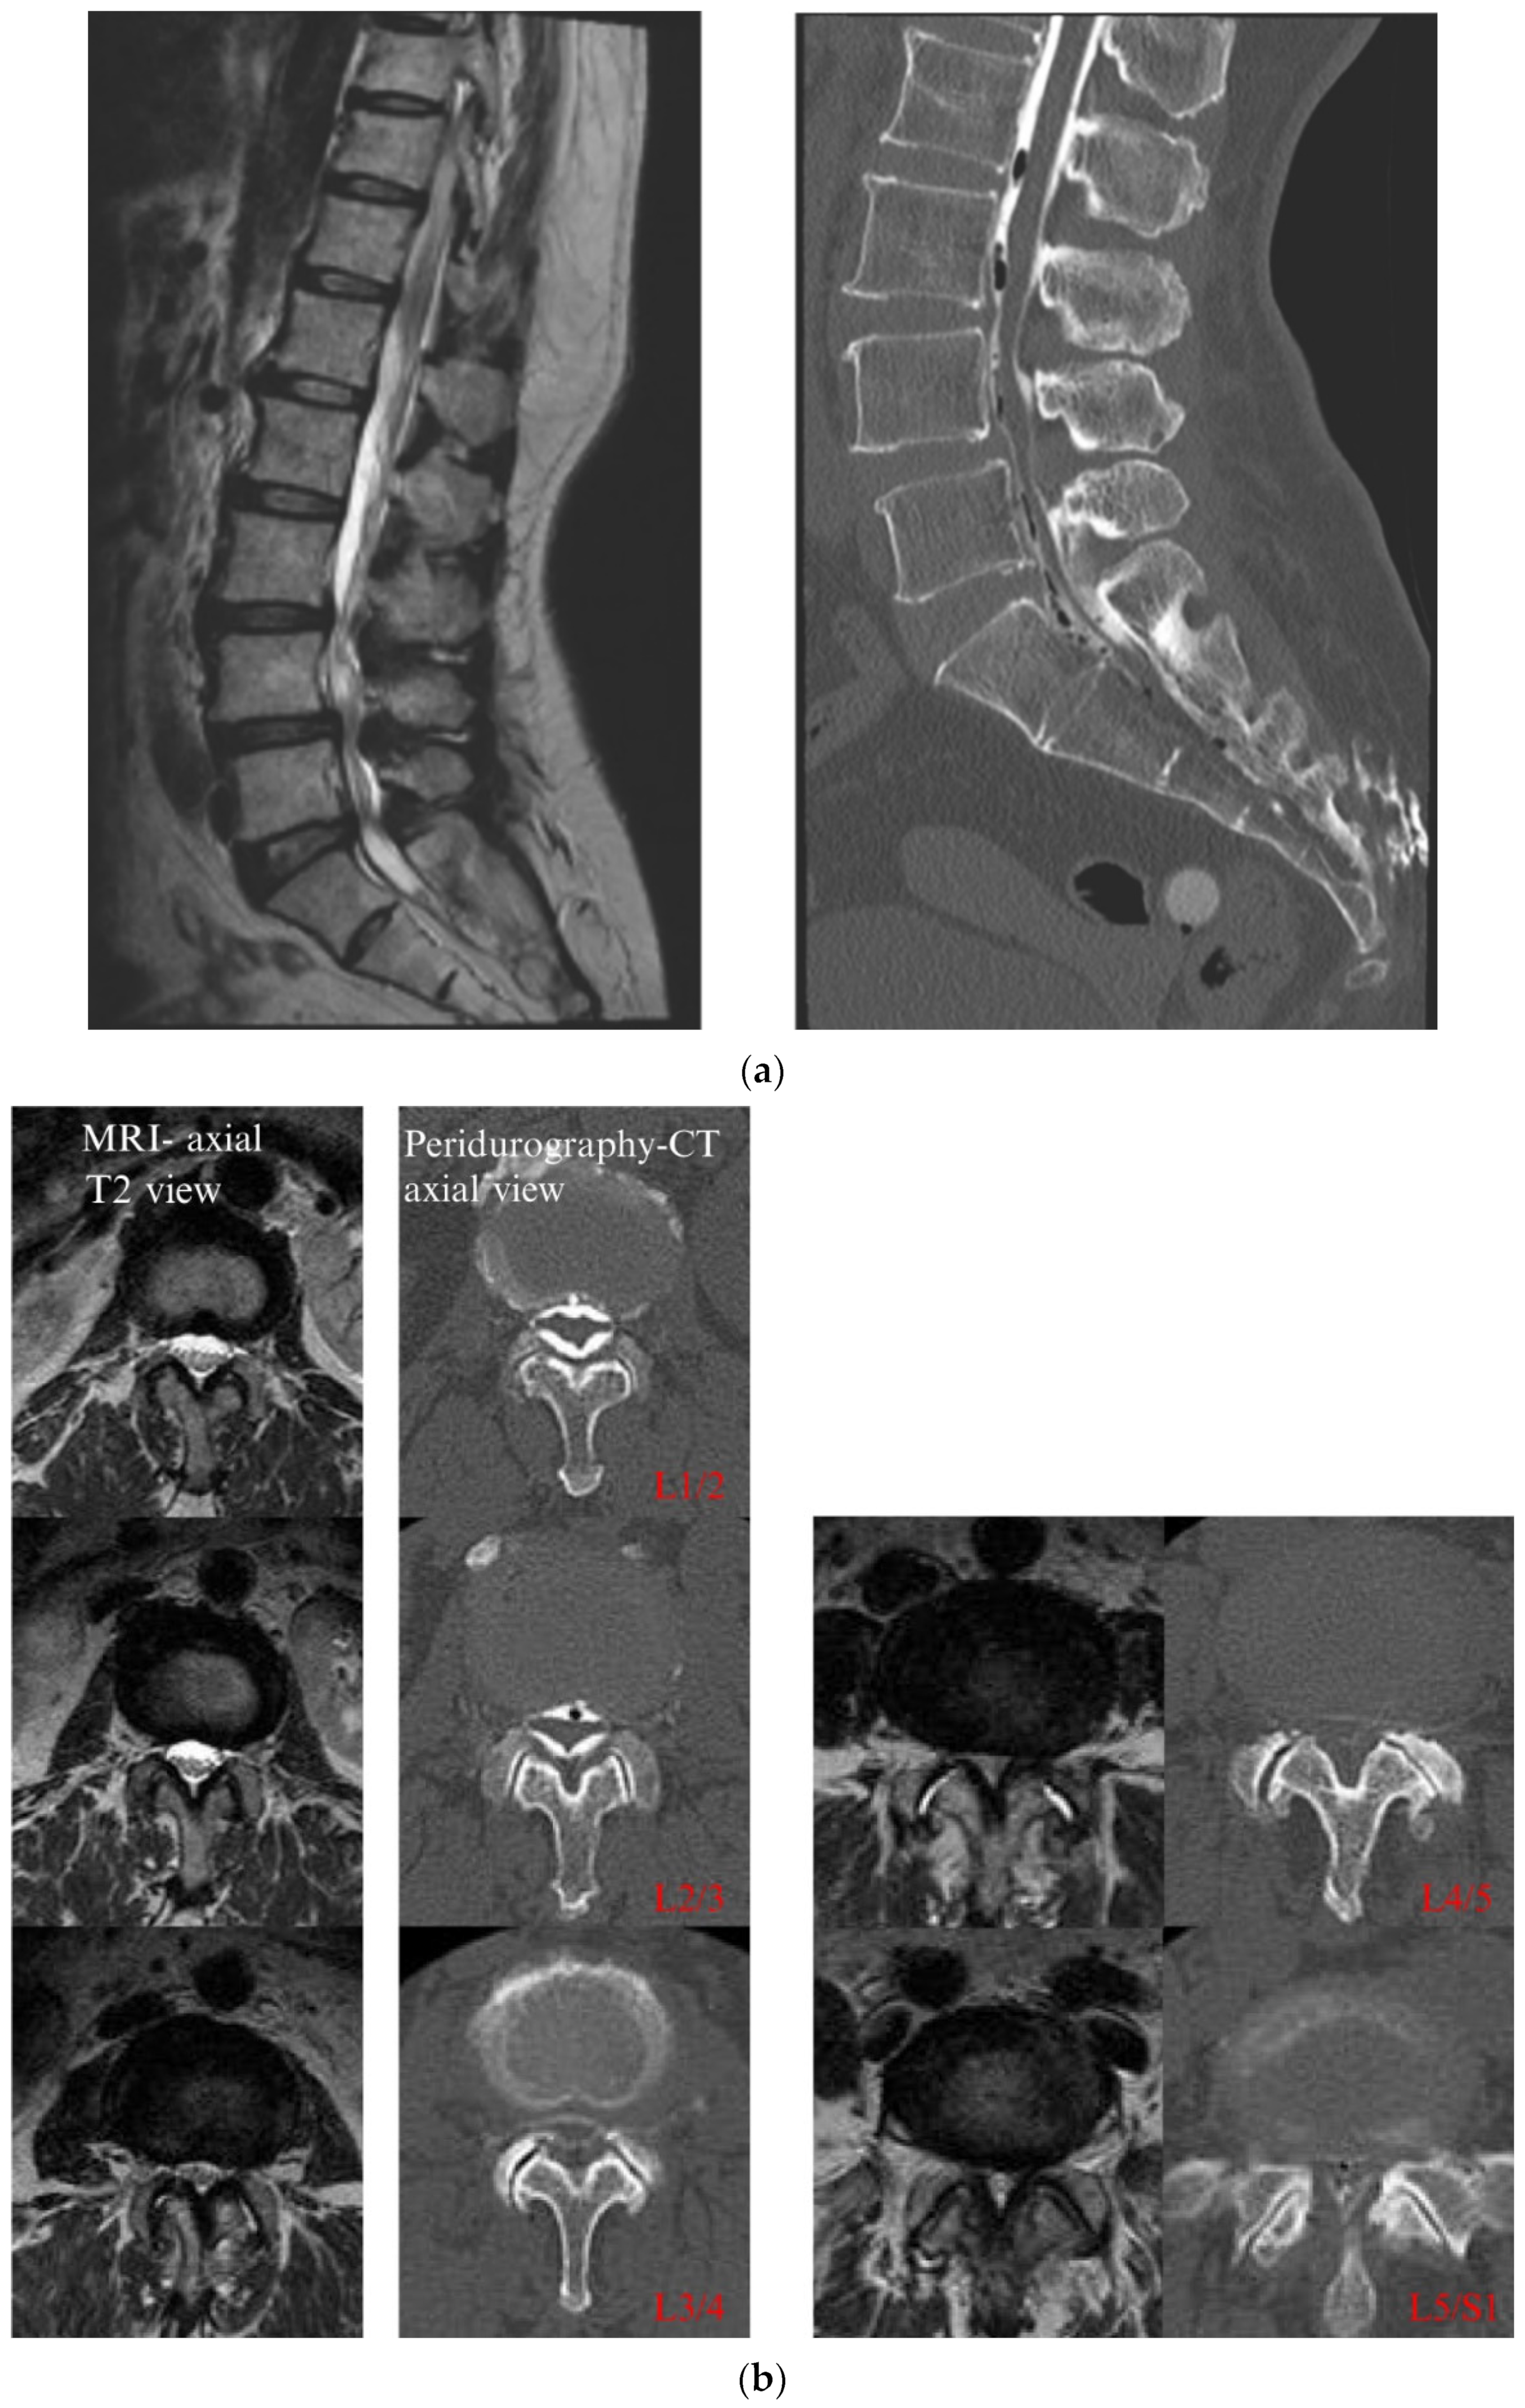

4.1. CT Epidurography